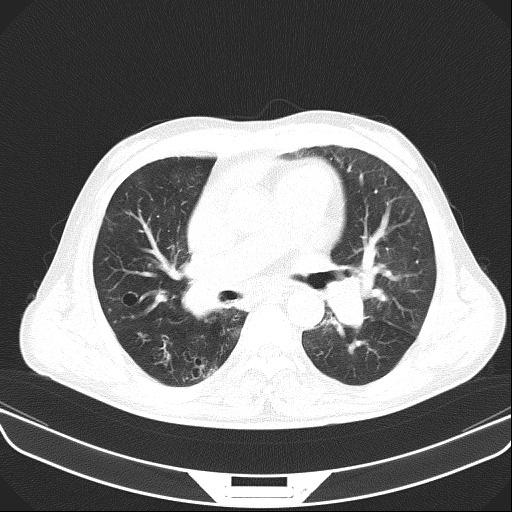

6月11日,会昌县人民医院呼吸内科接诊一呼吸衰竭的患者胡某,男性,54岁,主诉反复咳嗽、咳痰、气促10余年加重伴下肢浮肿10天入院。呼吸内科医生对胡某进行仔细查体:患者口唇及颜面、四肢紫绀明显,颈静脉怒张,桶状胸,肋间隙增宽,叩诊过清音,双肺呼吸音减弱,可闻及较多干湿性啰音,腹膨隆,肠鸣音减弱,双下肢重度浮肿。结合各类辅助检查,确诊胡某为“慢性阻塞性肺疾病、慢性呼吸衰竭、慢性肺源性心脏病失代偿期、重度肺动脉高压”。

按照常规,医生会建议患者转ICU气管插管接有创呼吸机辅助通气或者转上级医院救治,但胡某拒绝转ICU,拒绝转上级医院,不接受气管插管及面罩式无创呼吸机辅助通气。经科内医生组讨论后决定:为避免患者气管插管或切开,使用经鼻高流量氧疗治疗,同时配合抗感染,雾化解痉祛痰,甲泼尼龙、多索茶碱平喘,托拉塞米、螺内酯利尿等治疗。经过13天时间治疗,胡某症状缓解、浮肿消退,好转出院。

经鼻高流量氧疗(High-flow Nasal Cannula,HFNC)是指通过无需密封的鼻塞导管直接将一定氧浓度的空氧混合高流量气体输送给患者的一种氧疗方式。最初是为替代经鼻持续正压通气(NCPAP)的呼吸支持手段而广泛应用于新生儿呼吸窘迫综合征(NRDS),并取得了肯定的疗效。随着HFNC在成人的广泛应用,医务人员认识到它不同于普通氧疗及无创机械通气的独特优势:1、氧浓度恒定;2、良好的温湿化效果;3、呼气末正压(PEEP)效应;4、生理死腔冲刷效应;5、维持黏液纤毛清除系统功能;6、降低患者上气道阻力及呼吸功;7、舒适度和耐受性好。

临床上应用的特点:1、急性I型呼吸衰竭,能有效提高肺泡氧浓度,纠正呼吸衰竭;2、有创通气撤机,可以提高脱机的成功率,有效减少患者的再插管率,提高患者舒适度,缩短患者撤机时间,从而减少耐药菌感染的几率,增加治疗成功率;3、II型呼吸衰竭,因HFNC能给予呼气末正压,能有效减少生理死腔,对于意识清楚的II型呼吸衰竭患者,可以尝试使用,对于慢阻肺稳定期的患者可以用于改善运动耐力和生活质量。(陈琛)